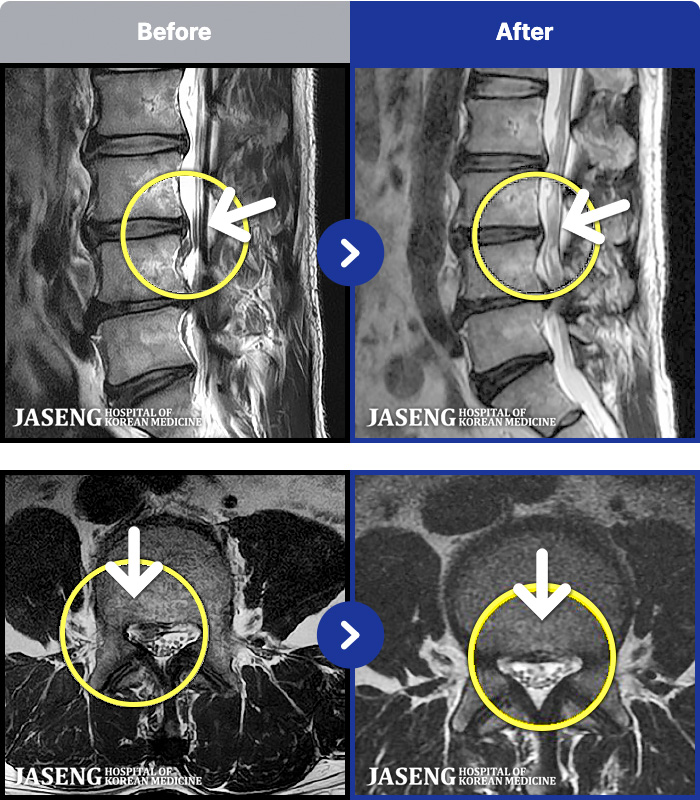

[Կñ:22.04.11~22.07.28]

[_㸮ũ] Ͽ ü Ÿ Ͽϴ.

No.54

ȸ 315

2026.01.09